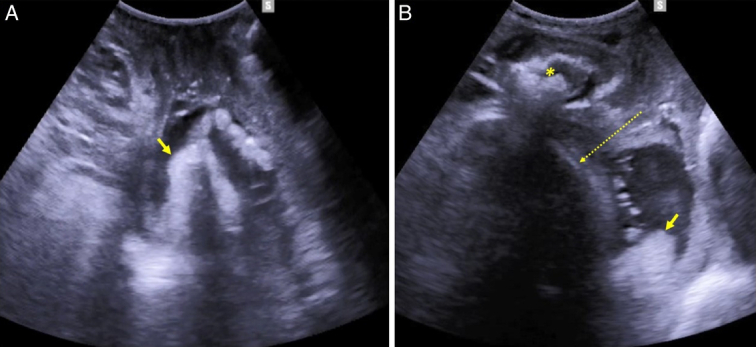

Intrapartum ultrasound (US) is more reliable than clinical assessment in determining parameters of crucial importance to optimize the management of labor including the position and station of the presenting part. Evidence from the literature supports the role of intrapartum US in predicting the outcome of labor in women diagnosed with slow progress during the first and second stage of labor, and randomized data have demonstrated that transabdominal US is far more accurate than digital examination in assessing fetal position before performing an instrumental delivery. Intrapartum US has also been shown to outperform the clinical skills in predicting the outcome and improving the technique of instrumental vaginal delivery. On this basis, some guidelines recommend intrapartum US to ascertain occiput position before performing an instrumental delivery. Manual rotation of occiput posterior position (MROP) and assisted breech delivery of the second twin are other obstetric interventions that can be performed during the second stage of labor with the support of intrapartum US. In this review article we summarize the existing evidence on the role of intrapartum US in assisting different types of obstetric intervention with the aim to improve their safety.